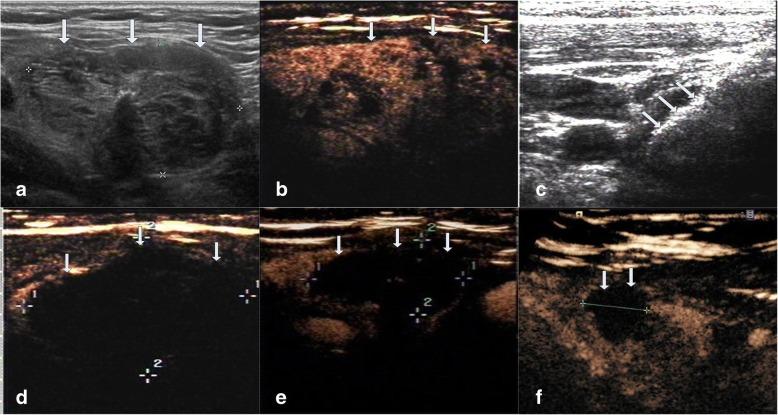

This retrospective study evaluated 194 non-functioning solid benign TNs of 103 patients. The TNs were categorized as small (≤5 ml), medium (5.1 to 13 ml), intermediate (13.1 to 30 ml) and large (over 30 ml) according to the initial volume of TNs before ablation. Clinical evaluation and contrast-enhanced ultrasound (CEUS) were carried out before ablation and the follow up at 1, 3, 6 months and every 6 months after ablation. All patients were asked to assess the cosmetic score (1-4 scores) and symptom score (0-10 scores) before ablation and every follow up after ablation.

方法